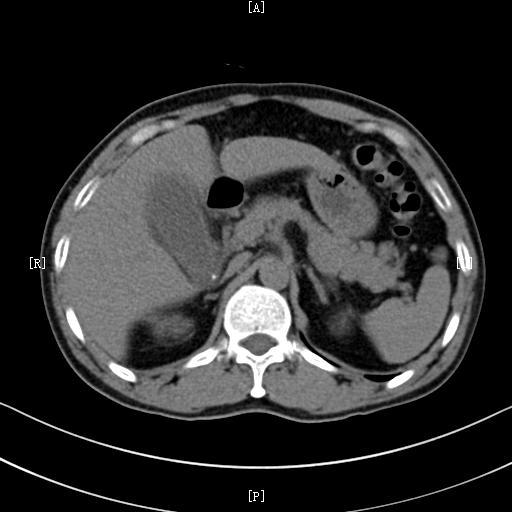

如果出现上述类似的症状,建议及时到医院筛查排出肝脓肿。主要的检查项目常常为 查血和超声检查 。实验室查血检查常常 白细胞计数明显增高 ;超声检查常常可以 明确其部位和大小 ,阳性诊断率可以达到95%以上,是首选检查;当然, 必要时也可以做CT检查 ,CT检查能够全面评估病灶以及周围脏器的情况,是非常好的一项辅助检查方法。

肝脏肿瘤的疼痛常常不是特别典型,所以及时筛查非常重要,对于肝癌,主要的筛查方法包括: 查血清甲胎蛋白(AFP),超声检查,CT检查和MRI检查 。AFP对肝癌有比较高的特异性,很多肝癌患者都有AFP的升高;而影像学的超声,CT和MRI检查是诊断肝癌以及其他肝脏肿瘤最主要的方法。

急性胆囊炎常常通过医生的 体格检查,结合查血,超声及CT检查 可以确诊。体格检查常常会有右上腹胆囊区域的压痛;查血常常会有白细胞的升高,而超声和CT检查可以观察胆囊大小,胆囊壁是否增厚,胆囊周围有无水肿,是诊断胆囊炎必不可少的辅助检查。

而对于胆囊及胆道结石的诊断,主要还是依靠 超声检查 。对于胆囊结石,超声诊断准确率一般都非常高,而对于部分胆道结石,需要借助CT或者MRCP检查进行确诊。

3、胆囊及胆道肿瘤。比如胆囊癌、胆管癌之类的。肿瘤引起的腹痛常常没有特异性,以隐痛比较多见。如果继发了胆囊炎,还可能和胆囊炎症状类似。所以对于胆囊肿瘤,最好的方法还是通过影像学检查明确。比较好的检查方法是CT或者MRI检查。

而如果怀疑是肾脏疾病,可以考虑进行 超声以及CT检查 ,影像学检查仍然是发现肾脏疾病最主要的方法。